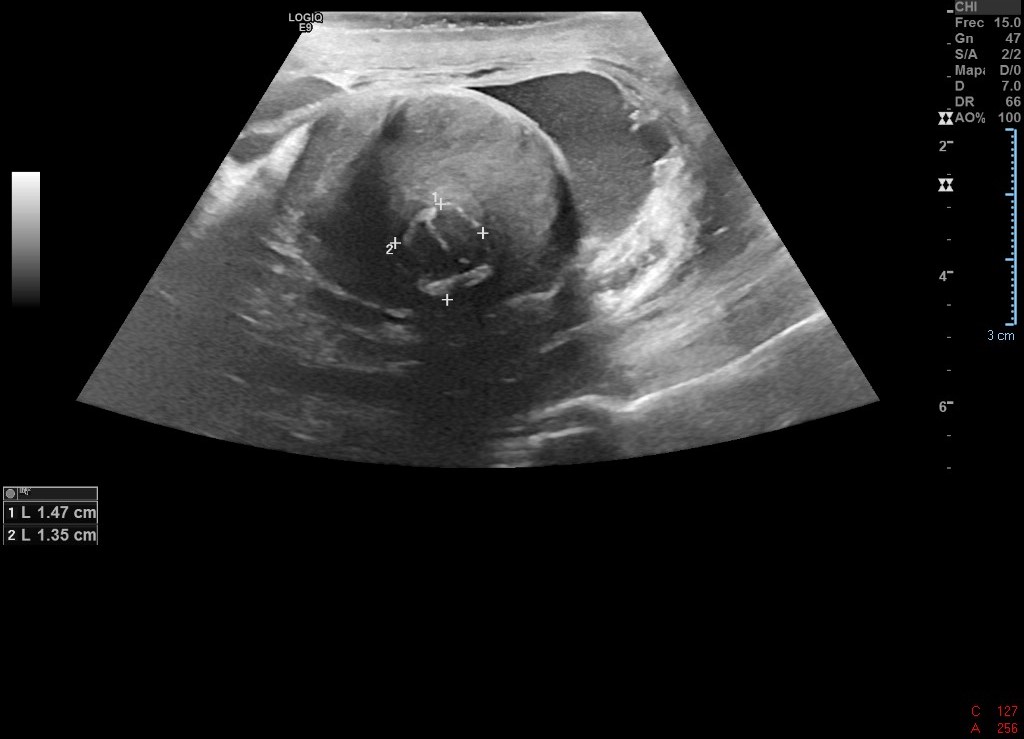

Ecografía de abdomen de Urgencias: se observa gran LOE pélvico abdominal ecogenicidad heterogénea, con hígado aumentado de tamaño y con imágenes hipoecoicas. Uterohidronefrosis derecha.

Durante el ingreso hospitalario se realizó biopsia de adenopatía que concluyó metastásis de neoplasia de estirpe germinal (posible Seminoma).

Igualmente se concluyó el estudio con ecografía de testículo y RNM.

En Atención Primaria, los meses previos fue tratado como una lumbalgia de cáracter crónico. La disnea por la que se derivó fue fruto de un TEP. El diagnóstico definitivo: Seminoma con hígado metastásico con adenopatías derechas y compresión de ilíaca derecha.